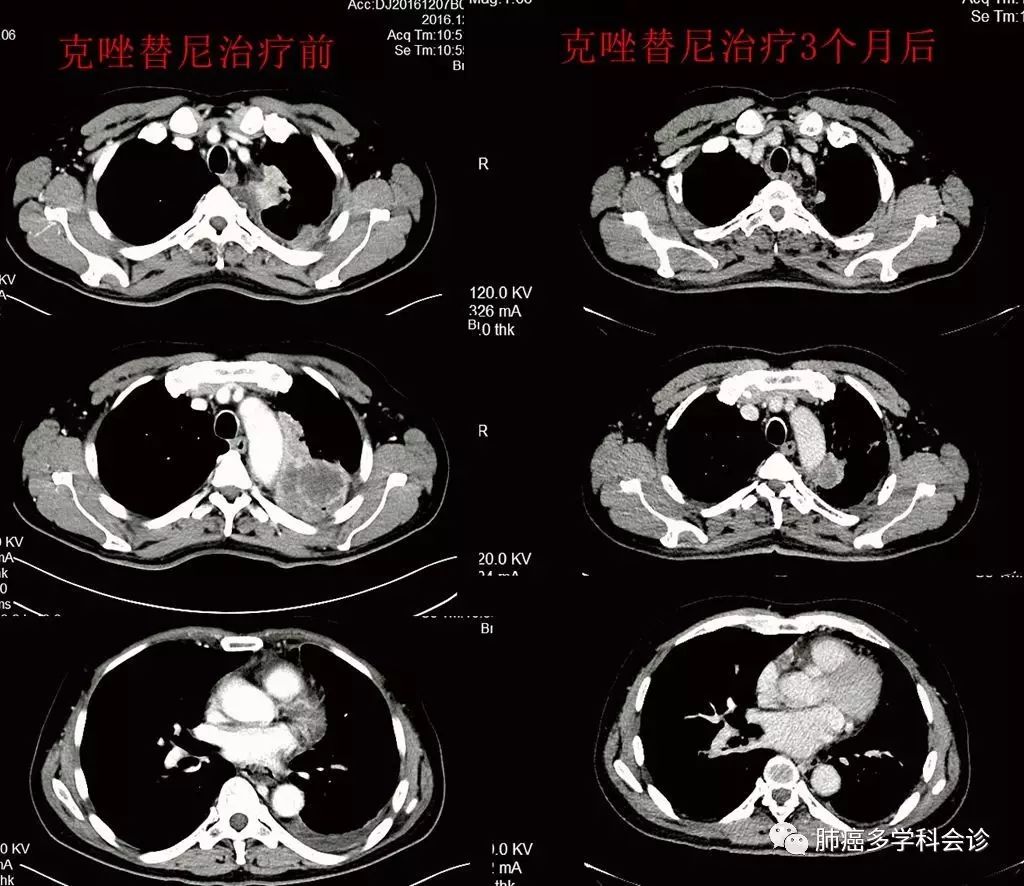

于2016-12-22开始口服克唑替尼,20余天后复查CT示病灶稳定,3月后复查CT示疗效PR,肿瘤标志物 CA19-9 明显下降。